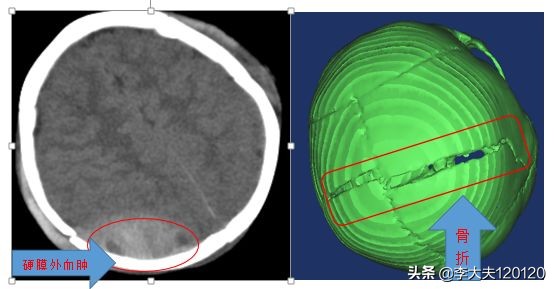

急诊查头颅CT:双侧额顶部硬膜外血肿、顶骨骨折、顶枕部皮下血肿。

见到患儿时,患儿处于昏睡态势,急诊头颅CT显示“硬膜外血肿、顶骨骨折”, 情况非常危急。